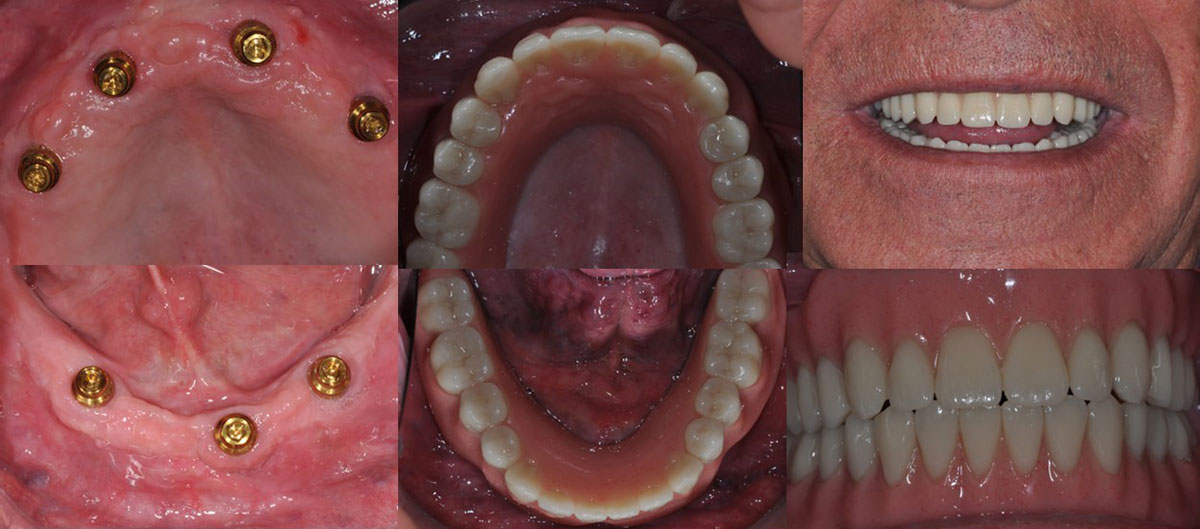

Lo más recomendable es, siempre, reponer los dientes perdidos. Para ello contamos con distintas opciones protésicas adaptadas a las necesidades, requerimientos y posibilidades de cada paciente. Desde las tradicionales prótesis removibles convencionales hasta los más modernos tratamientos con implantes, disponemos de todo un abanico de posibilidades encaminadas a restaurar la función y la estética de nuestros pacientes según sus particularidades.